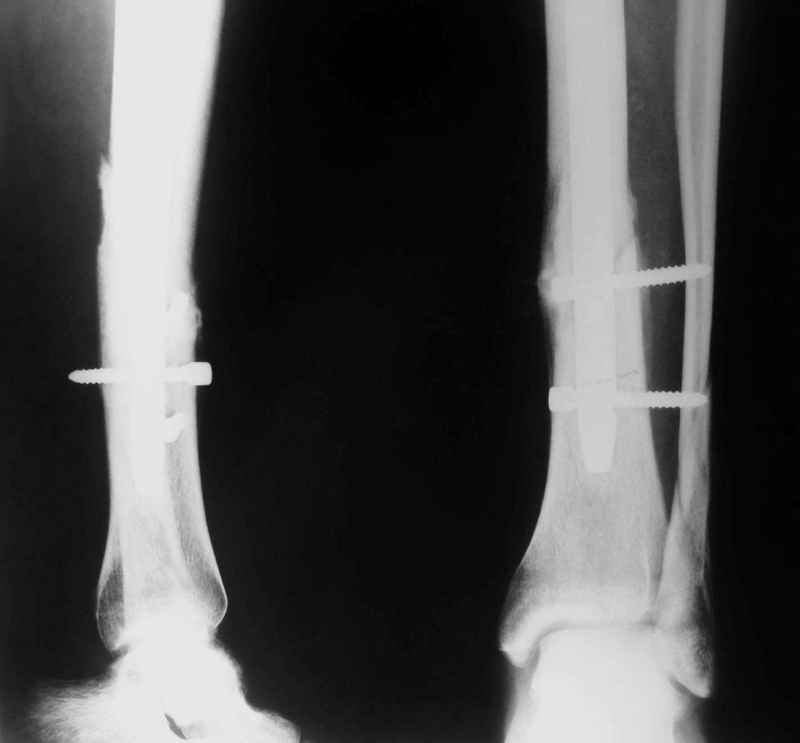

В 2002 г. была у нас больная с ложным суставом бедра и остеомиелитом (как оказалось), после удаления пластины. Гвоздь с блокированием.

Потекло через месяц - открылось 2 свища по старому рубцу от давно удаленной пластины. На фоне гноя раза три завинчивал обратно винты, которые вылезали латерально, прямо через свищ. Потом таки провел дополнительно винты мимо гвоздя, и убрал вверху статический винт. Острый гнойный процесс стих, свищи мыла она дома дважды в день водным хлоргексидином, ходила с возрастающей нагрузкой, а к 10 мес. и свищи закрылись, и срослось. Итоговые снимки от 18 апреля 2003 г. прилагаю.

Перелом спиральный, то есть низкоэнергетический, так что со сращением дело обстоит уже неплохо, лишь бы "костоеда" не развилась. Отломки выглядят уже стабилизированными костной мозолью, так что довводить винты, наверно, уже незачем. Разве что при клинической оценке подвижность еще есть - тогда можно для стабилизации наложить простейший аппарат, не опасаясь контакта его элементов с гвоздем, поскольку места в дистальном метафизе оставлено более чем достаточно.

С Александром согласен, нет необходимости делать дополнительные усилия для сращения, не большая компрессия аппаратом из двух колец и полная нагрузка доделает работу.